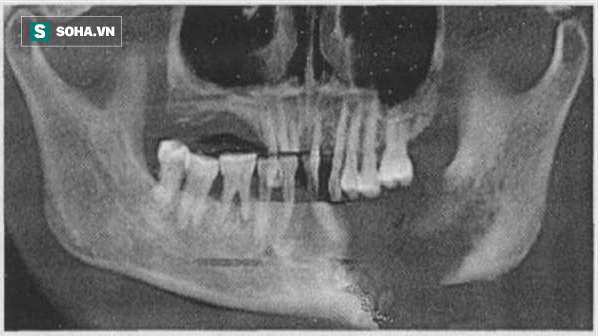

Hơn thế nữa, vùng nướu bên trái sưng to và mưng mủ, mủ lây sang cả vòm trong má, loét cục bộ vùng khoang miệng. Nhập viện và điều trị tại khoa Răng Hàm Mặt bệnh viện Vũ Hán (TQ), bác sĩ kiểm tra phát hiện vùng xương hàm bên trái của bệnh nhân đã bị hỏng nghiêm trọng.

Phần tủy xương của xương quai hàm cũng bị viêm và gần như hoại tử vùng hàm trái chứ không chỉ riêng phần răng bị hỏng.

Theo các bác sĩ, vấn đề của nam bệnh nhân này đã để kéo dài tình trạng sưng viêm quá lâu, hiện cần phải kiểm soát nhiễm trùng trước khi tìm phương án điều trị phù hợp. Trong ngắn hạn, buộc phải nhổ bỏ những chiếc răng đã hỏng không thể sửa chữa, sau đó tiến hoành khoét sửa vùng xương hàm bị hỏng tủy để khôi phục trong khả năng ít tổn thương nhất có thể.